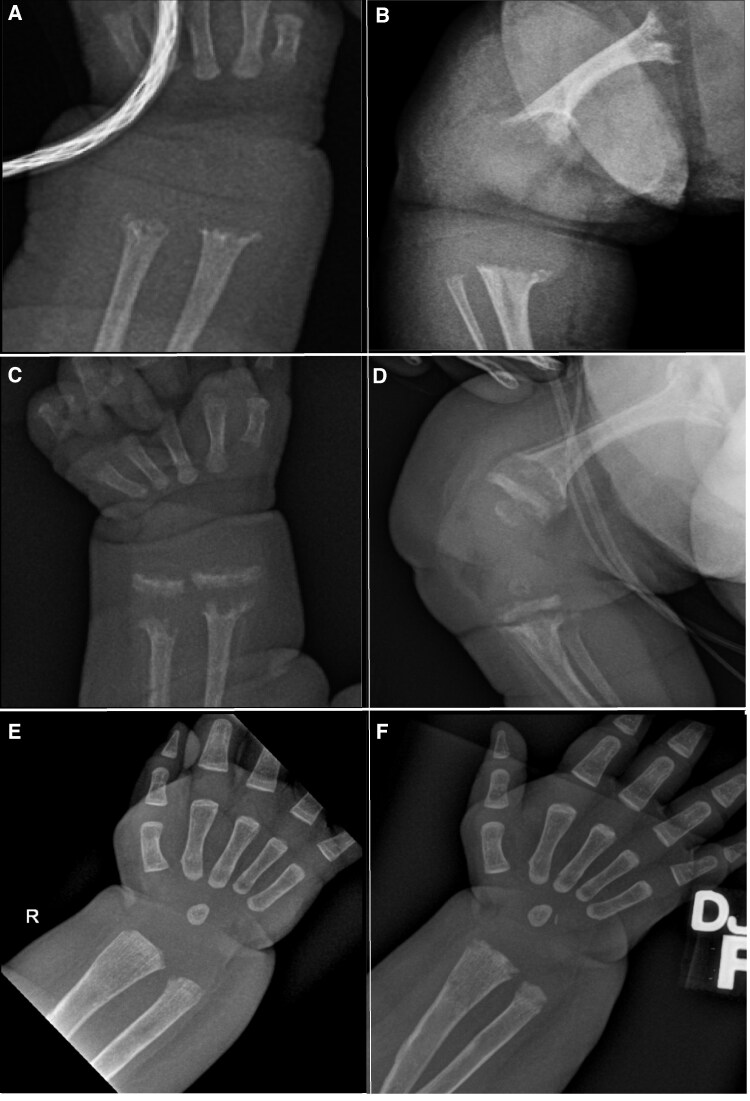

Abstract Image